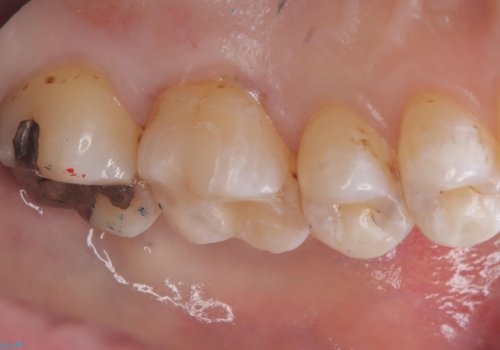

- 主訴:銀の詰め物が外れてしまった

保険適応のメタルインレーが脱離し、中が少し虫歯になっていたため審美性も良いセラミックインレーでのやり替えとなりました。

旧インレー窩洞内のカリエスと裏層を除去し、新たにCR裏層したうえでセラミックインレー修復を行いました。セラミックインレーセット時は、ラバーダム防湿を行っています。